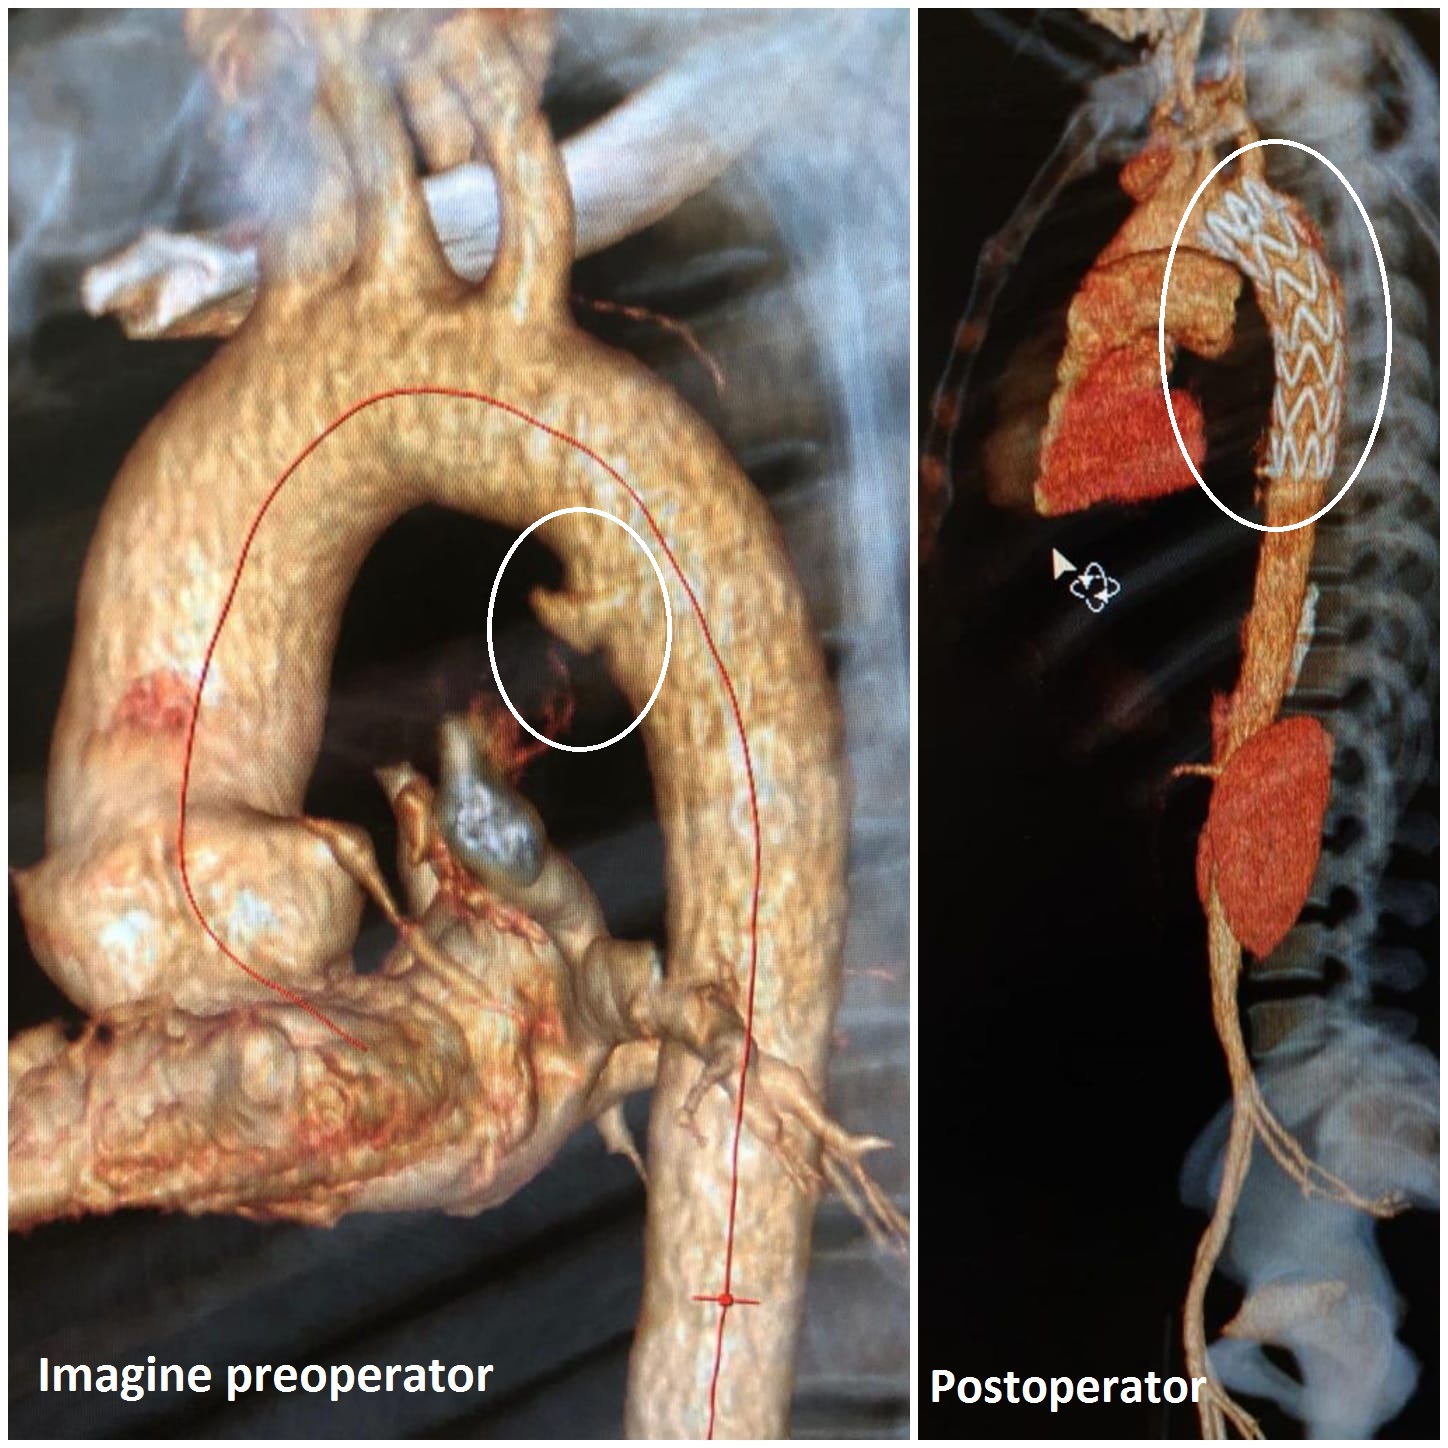

Pacientul a ajuns cu politraumatism la Unitatea de Primiri Urgențe, a fost examinat la computerul tomograf cu substanță de contrast, pe bază căruia s-a găsit leziunea aortică, o rană care, deși abia vizibilă, l-ar fi costat viața. Medicii, puși în fața unui asemenea diagnostic grav, au luat o decizie în regim de urgență și i-au montat, pe aortă, printr-un procedeu revoluționar, o proteză potrivită.

"Pacientul avea o fisură de aortă toracică, și am decis montarea, în Urgență, a unei endoproteze de aortă toracică pe cale femurală stângă, pentru acoperirea zonei de fisură aortică", spune dr. Dragoș Trandafir, coordonatorul secției de Chirurgie Vasculară din cadrul Spitalului Universitar."Fisura era pe aortă descendentă și pentru că exista riscul să se rupă mai rău, am decis montarea protezei, aceasta fiind procedura cea mai puțin riscantă pentru pacient. Practic, am montat un manșon, să-i spunem așa, pe interiorul vasului fisurat, pentru a preveni o ruptură.

Endoprotezarea este o procedura minim-invazivă și constă în introducerea unui tub din material sintetic în interiorul anevrismului, prin incizii făcute la nivel inghinal pe calea arterei femurale. Față de intervenția chirurgicală standard, endoprotezarea se realizează într-un timp mult mai scurt, incidența complicațiilor postoperatorii este diminuată, iar pacientul se recuperează mult mai rapid.